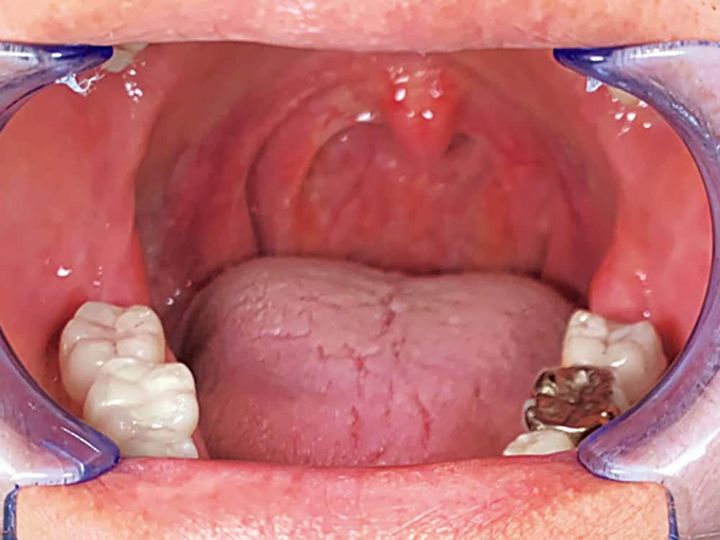

◇ HOT TO「舌の筋トレ」

① 舌を吸い上げて上あごにくっつける

口を開けて舌全体を上顎に吸い上げて20秒キープする。舌裏に洞窟を2つ作り、2分間繰り返す。

② 喉の奥で“カッ”と鳴らす

<1>

<2>

喉と舌の奥の筋肉をトレーニングすると、口蓋垂(喉ちんこのあたり)を鍛えられる。喉をしっかり上下させ音を鳴らして。

③ 舌を根元から動かして“ベー”!

舌をあごにつける気持ちで下に「ベー」と出す。舌の落ち込みを防ぐことでいびきを改善。

これができるようになったらGOAL!

口を閉じたときに、舌が上あごにくっつく定位置にきたらOK!